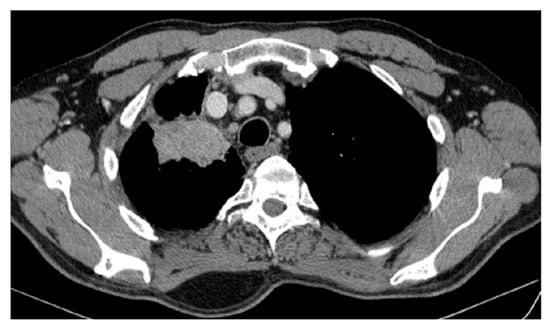

2. Case Presentation

2.2. Monitoring 2022: Oncological Commission 1910/16.08.2022

2.3. Oncological Committee 07/25/2023 Recommended

- Consider rescue re-irradiation (SBRT), taking into account the current primary tumor dimensions of 24 × 34.2 mm on PET CT from 06/2023 and also the total dose previously administered (08–09/2020), the previously applied fractionation, the time between the two irradiations, the cellular repair time and the dose constraints for the organs at risk.

| DOWNSTAGING from metastatic to locoregional stage | From cT3N3M1b(OSS) stage IVA | In cT2bN3M0, stage IIIB (without M1OSS) |